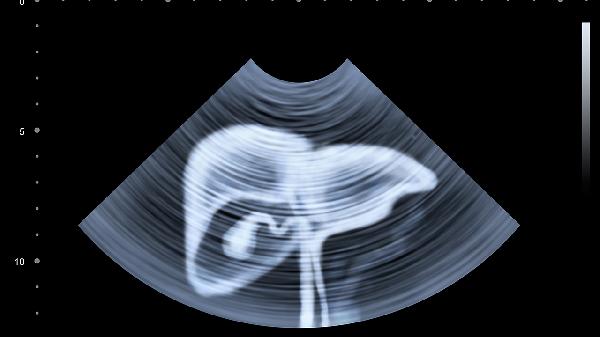

丙肝患者日常需保持均衡饮食,适量摄入优质蛋白质如鱼肉豆制品,限制高脂食物减轻肝脏负担。规律进行太极拳、散步等低强度运动,避免剧烈运动诱发疲劳。严格戒酒防止加速肝纤维化,每日睡眠不少于7小时。家庭成员应接种甲肝乙肝疫苗,避免合并感染加重肝损伤。出现食欲减退、皮肤黄染等症状时需及时复查肝功能与肝脏超声。